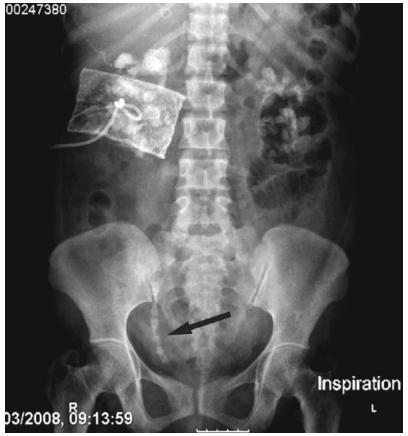

Nếu nhiều hơn 2 mảnh sỏi nằm trên niệu quản và dẫn đến tắc nghẽn thận thì được gọi là chuỗi sỏi (steinstrasse). Thông thường 1 mảnh sỏi lớn sẽ gây tắc nghẽn niệu quản trước, sau đó những mảnh sỏi sau sẽ mắc kẹt ở phía trên.

10

Hình 10.Chuỗi sỏi niệu quản phải đoạn chậu sau TSNCT

ở bệnh nhân mang sỏi san hô được điều trị kết hợp TSNCT và LSTQD

Nguyên nhân dẫn đến chuỗi sỏi thường là do kích thước viên sỏi ban đầu lớn, vì vậy những viên sỏi > 2,5cm đều được khuyến cáo là không phù hợp với TSNCT.

Vị trí chuỗi sỏi thường gặp nhất là niệu quản đoạn xa (64%), kế đó là đoạn gần (29%) và cuối cùng là đoạn giữa (8%).